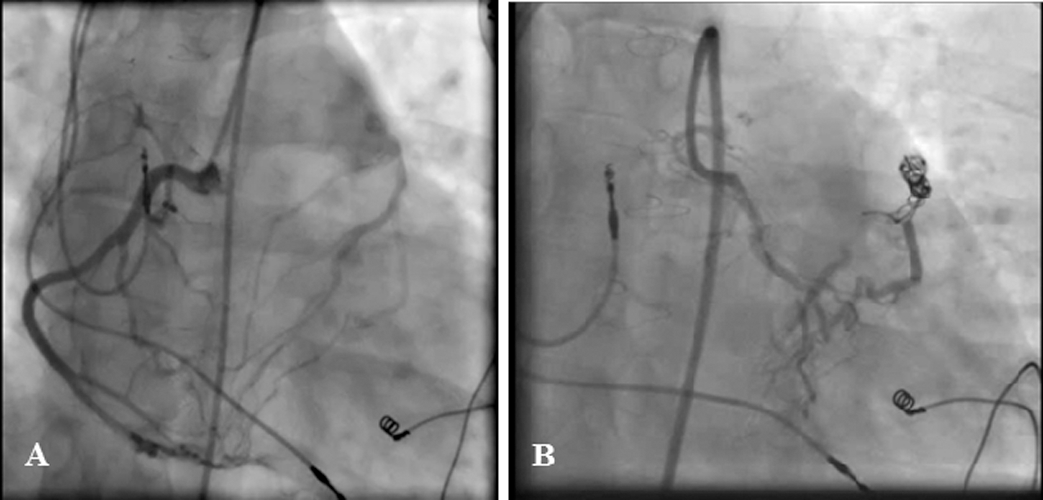

Physical examination showed normal S1 and S2 and audible loud continuous murmurs at the upper left sternal border. Chest radiography showed mild cardiomegaly, RV enlargement, and shunt vascularity. Left coronary injection helped visualize a small fistula from the septal branch of the LAD to the main pulmonary artery. Right coronary artery injection showed a developed fistula with multiple feeding branches from the RV branches and also the distal portion of the right coronary artery (the posterior descending artery and the posterolateral branch) to the main pulmonary artery with a single drainage site. The fistula appeared to be congenital in origin with hemodynamic effects having become more prominent in adulthood. For CAF closure, a microcatheter (Caravel, ASAHI INTECC, Japan) was introduced from the larger RV branch to the distal part of the CAF in close proximity to the pulmonary artery. Additionally, a right Judkins guiding catheter was placed at the exit of the CAF via the venous access. Two coils (7 mm × 30 cm MicroPlex-10, MicroVention-Terumo, Japan, and 7 mm × 40 cm Cook UK Ltd.) were released successfully with the aid of the microcatheter. The final injection showed no residual shunt (Fig. 3). At 1 month’s follow-up, the patient was completely asymptomatic. CTA confirmed no residual shunt and showed proper coil position.

Figure 3: Right coronary artery injection illustrates a developed fistula with frequent feeding branches from the right ventricular branches and also the distal branches of the right coronary artery to the main pulmonary artery with a single drainage site (Fig. A). For the closure of the coronary artery fistula, a microcatheter was introduced from the larger right ventricular branch to the distal part of the fistula near the pulmonary artery. In addition, a right Judkins guiding catheter was placed at the exit site of the coronary artery fistula through the vein access. Two coils were released successfully by using the microcatheter. The final injection showed no residual shunt (Fig. B)